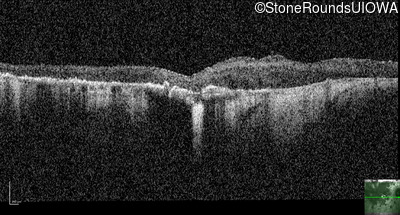

Optical Coherence Tomography - Right - 10/600 sc

Exemplar / OCT Stack

Optical Coherence Tomography - Left - 10/600 sc